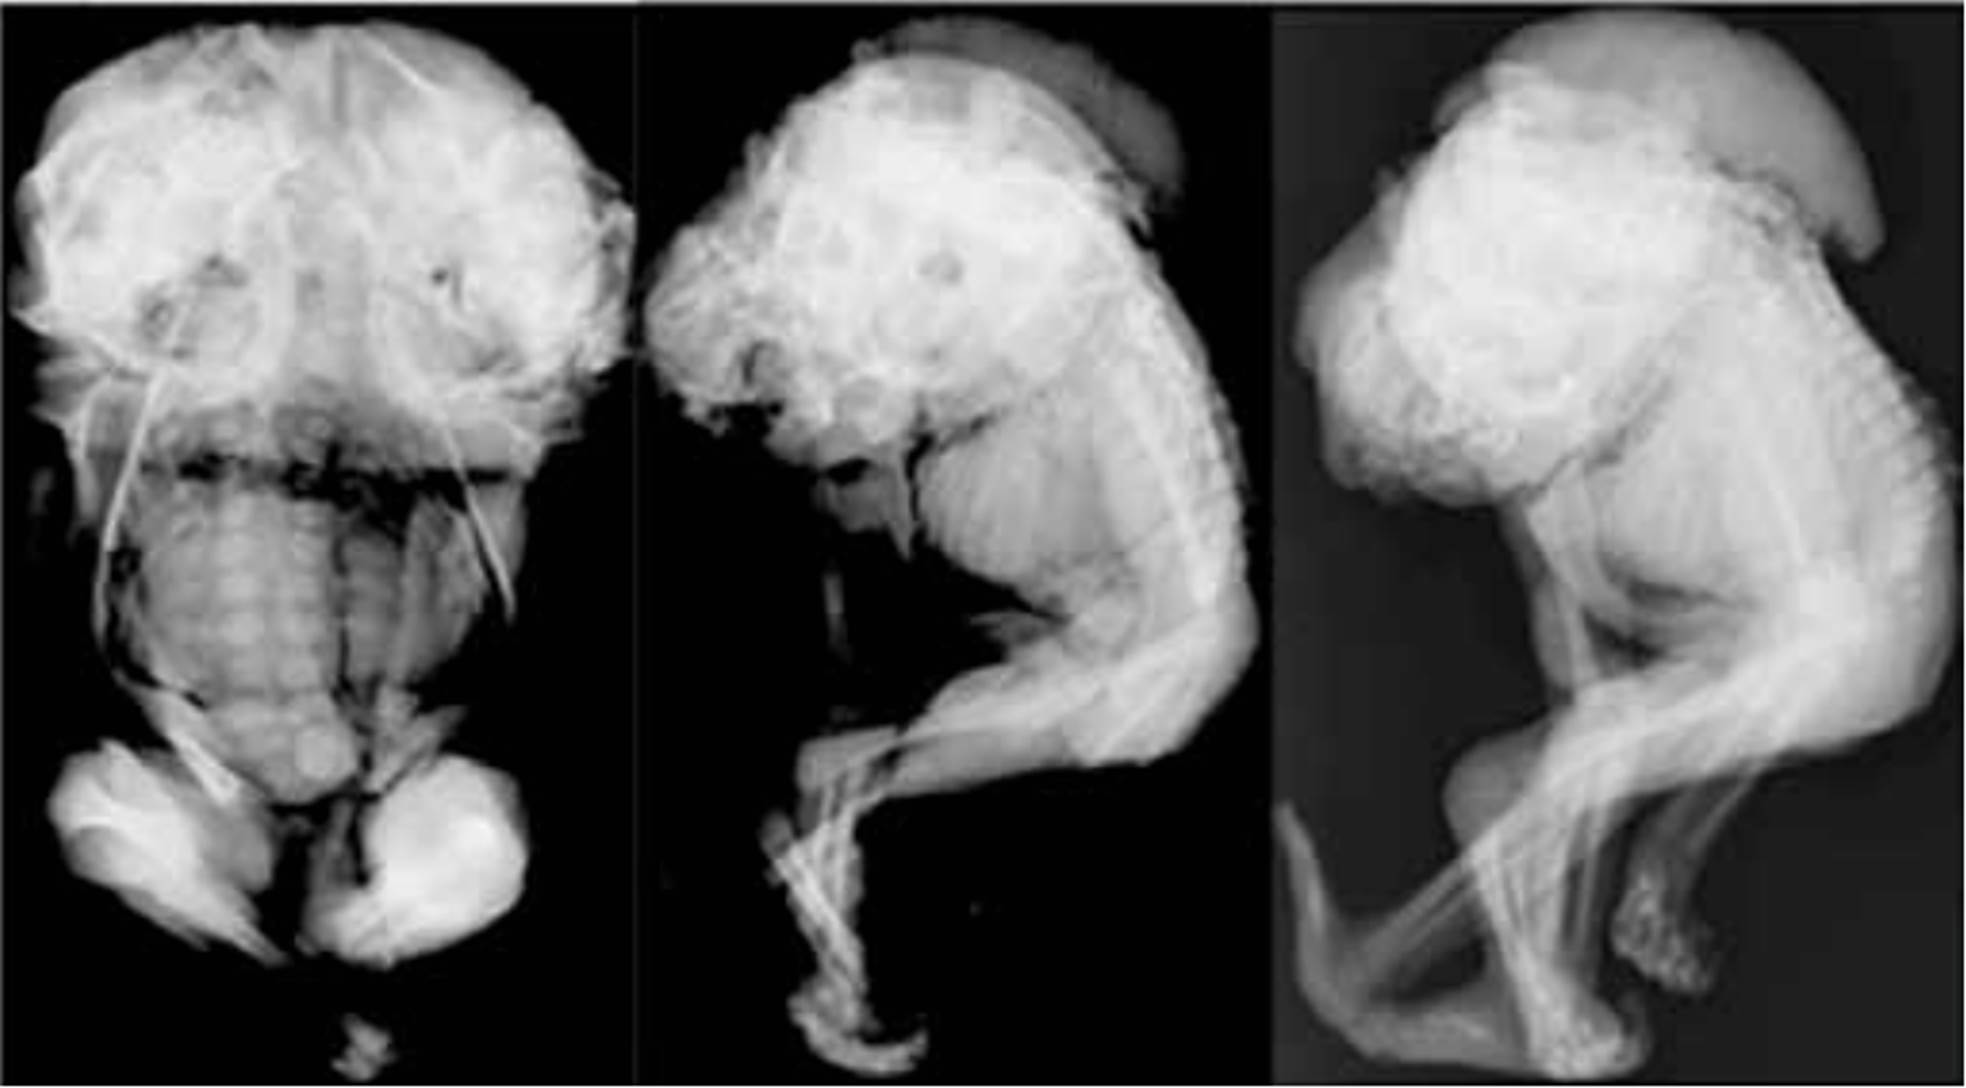

Se practicaron radiografías convencionales en un centro de imagenología privado de la ciudad, empleándose un equipo Philips DSI, PHILIPS DSI SUPER 80CP, diagnostics 76 plus, sobre el cual se ubicó el espécimen fetal en proyecciones A-P, P-A y laterales.

Los hallazgos Imageneológicos por medio del empleo de radiología convencional permitieron identificar en sus imágenes: (Ver figura No. 2)

Figura Nro 2.  A. Espécimen en Vista AP supino. B Vista lateral derecha AP supino. C. Vista lateral izquierda AP supino.

Descripción macroscópica. Feto único de 25 semanas, observándose bicéfalo con presencia de grandes defectos de fusión de la columna, desde la columna lumbar alta, la columna dorsal y la cervical; las soluciones de continuidad o defectos de la línea media descritos producen gran mielomeningocele. Los tejidos blandos a nivel del cuello están fusionados. La columna es única, se evidencia marcada roto escoliosis, principalmente a nivel de la columna dorsal que produce deformidad de la caja torácica.

Es de notable importancia la presencia de encefalocele occipital completo y bilateral, con marcada deformidad de las bóvedas craneales en número de dos, con aplanamiento y ensanchamiento lateral. Las bóvedas craneanas están vacías secundario al encefalocele completo descrito de ambos cráneos, coexistiendo un aplanamiento frontal ángulo frontomaxilar aumentado con defecto de la línea media de la cara, labio y paladar hendidos de ambas caras de forma simétrica acompañado de exoftalmos; las demás estructuras de las dos caras no presentan alteraciones significativas.

La región toracoabdominal es de morfología normal y corta; no se evalúan las vísceras en las imágenes evaluadas. Las estructuras óseas son de morfología normal, no hay alteraciones en la diáfisis, metáfisis o epífisis de los huesos largos; se evidencia aumento en la longitud de los huesos largos de ambos miembros superiores: húmeros, radiales y cubitales, aunque su morfología es normal; no hay soluciones de continuidad ni defectos corticales.

A nivel del miembro superior se evidenció que los huesos del carpo y las falanges son simétricos y de morfología normal; respecto a los miembros inferiores los pies se encuentran simétricos y sin alteraciones, solo abundantes vellosidades (hirsutismo).